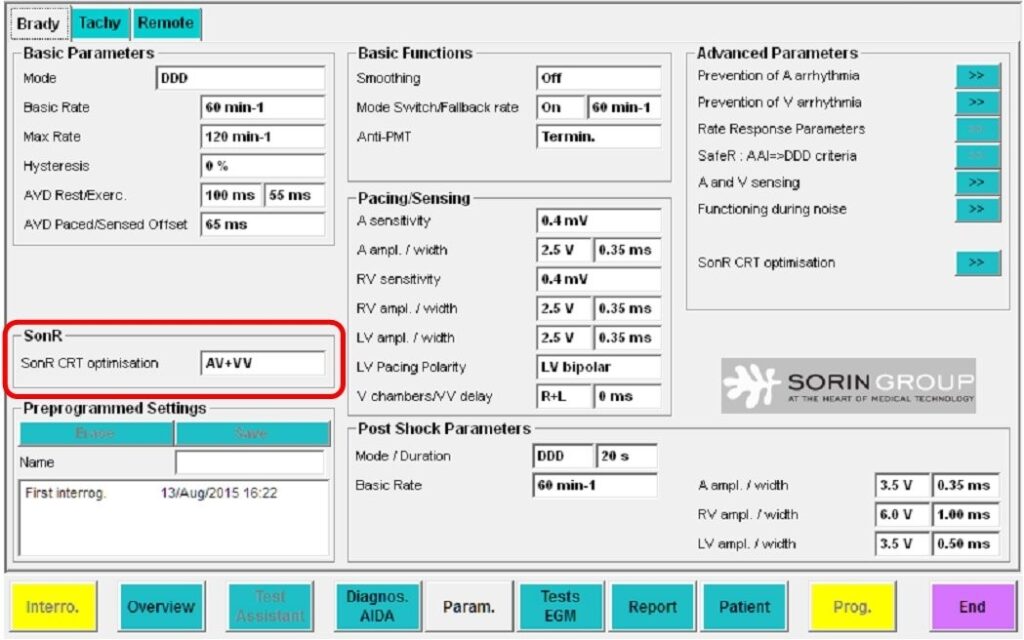

Les systèmes CRT-D SonR numérisent et analysent le signal SonR1 provenant de la sonde auriculaire. L'algorithme contenu dans ces défibrillateurs optimise automatiquement les délais AV et VV sur une base hebdomadaire.

Test manuel

Des tests d'optimisation des délais AV/ VV peuvent également être réalisés au cours du suivi du patient, y compris avec la configuration LV only.